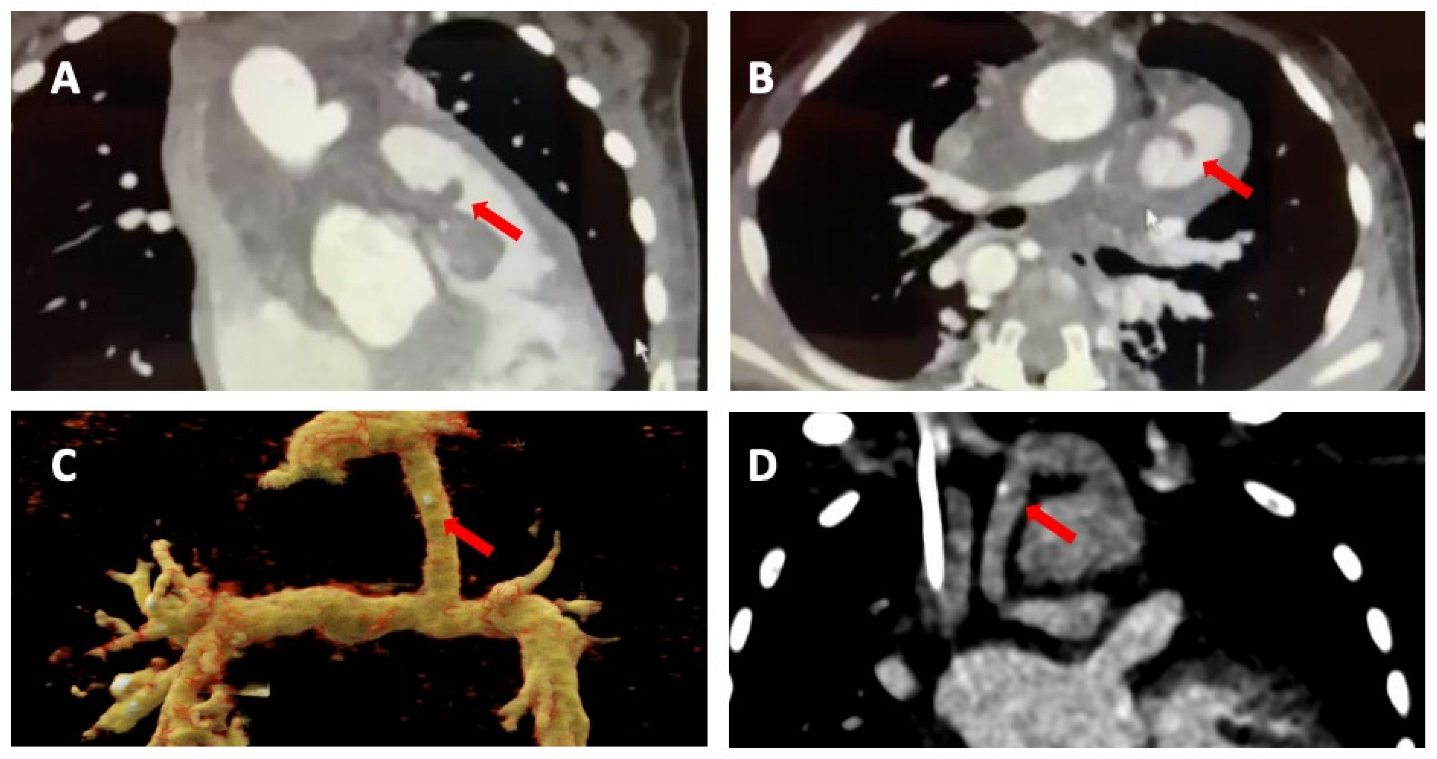

Figure 3. Cardiac computed tomography infective endocarditis visualisation. The images show right-ventricular pulmonary artery (RV-PA) conduit involvement (panels (A,B)) and systemic to pulmonary shunt involvement with a calcified lesion (panel (C,D)). The arrows indicate the vegetations.